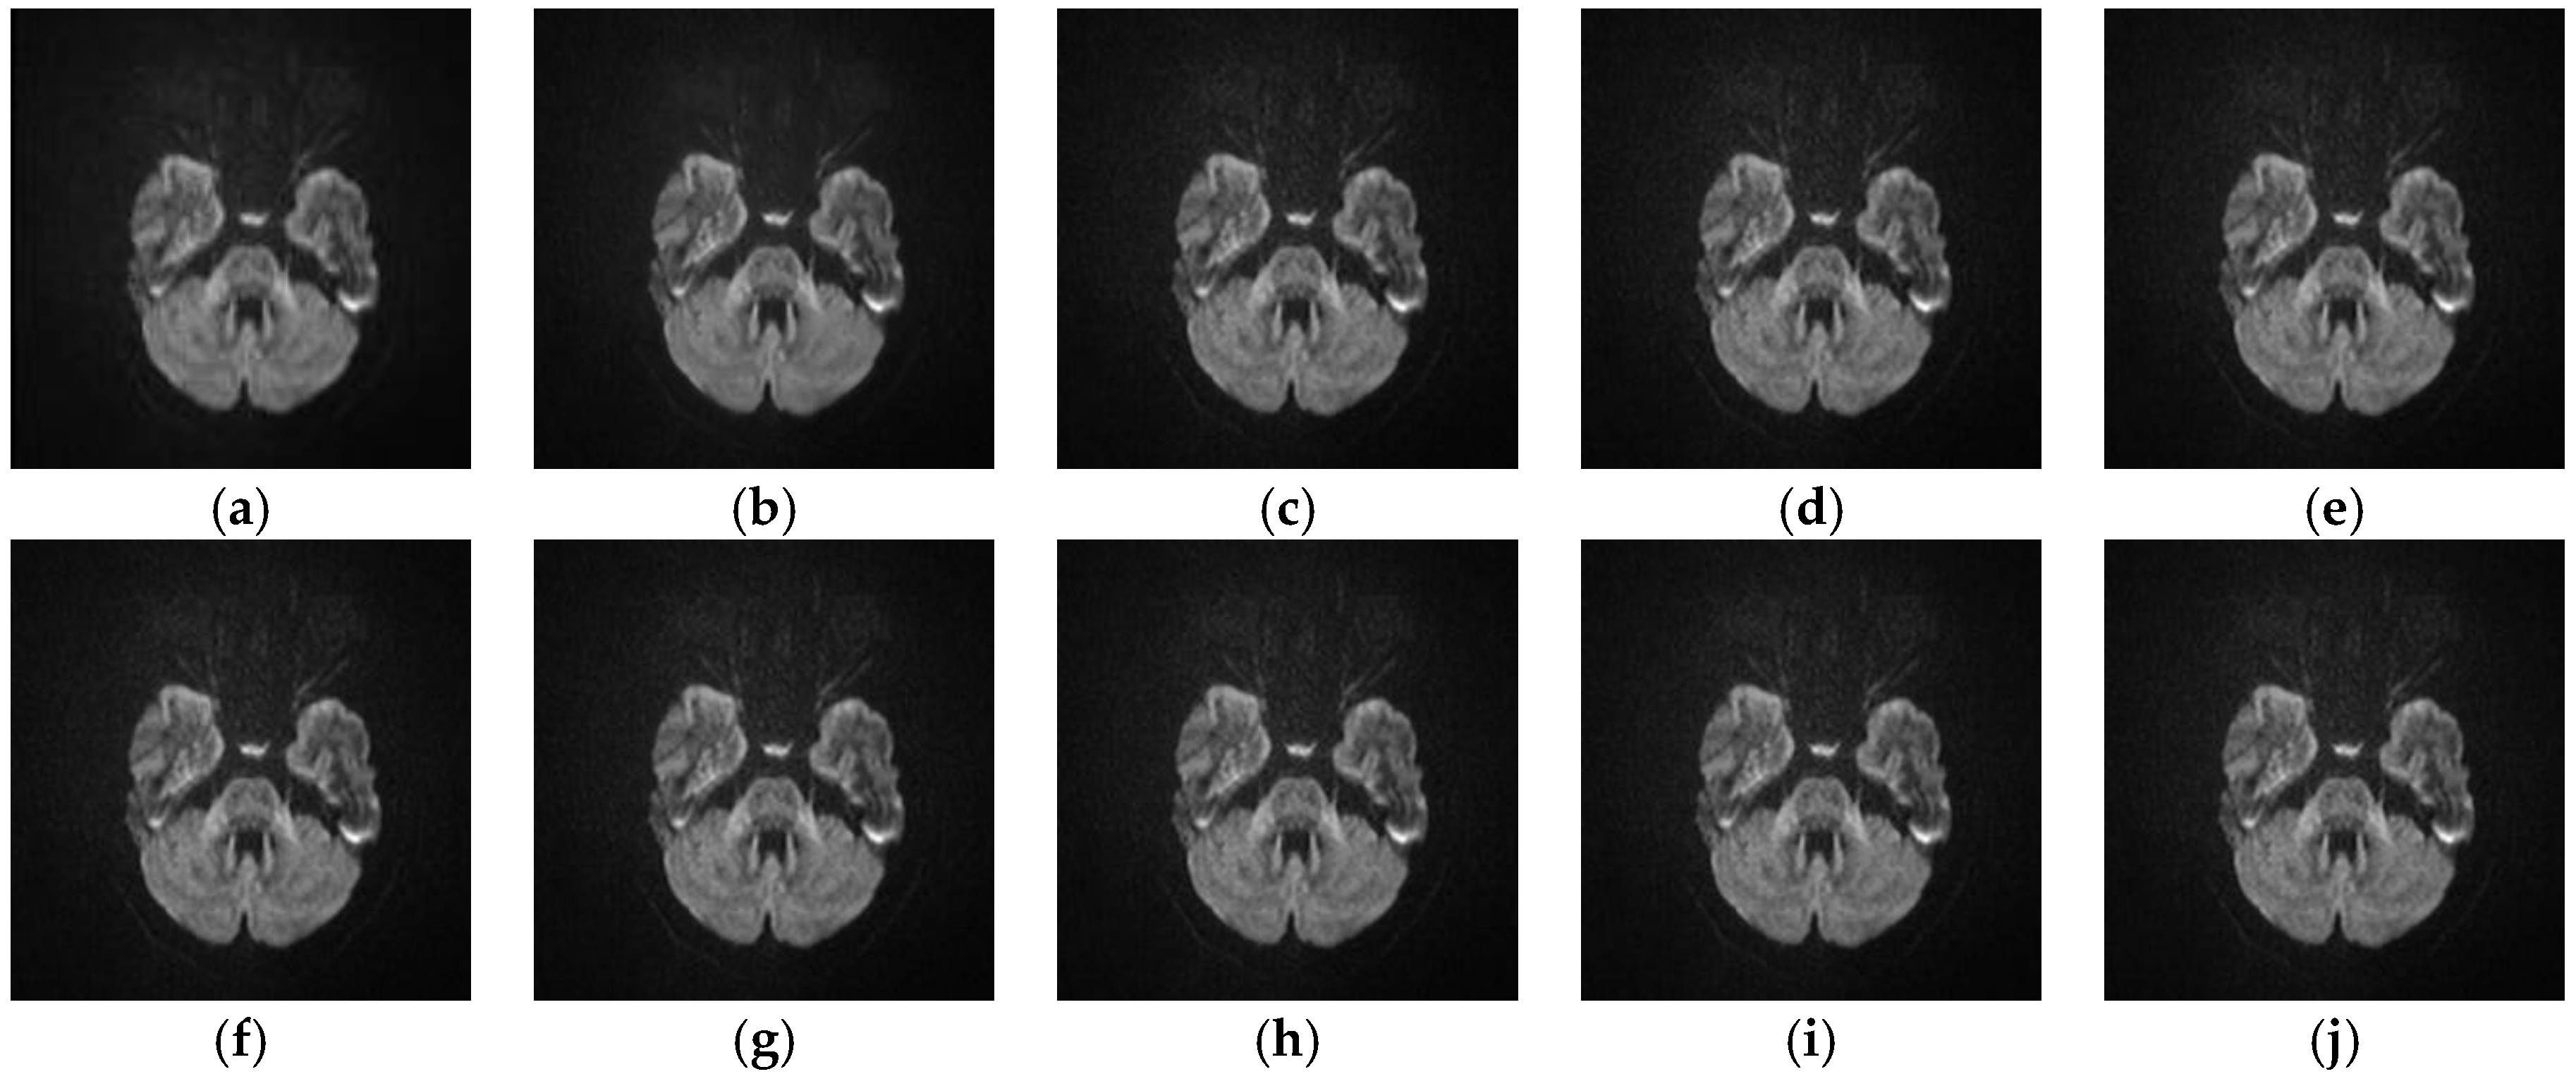

5.2.4. Analyze the Performance of Different SR Algorithms on Real Medical Images